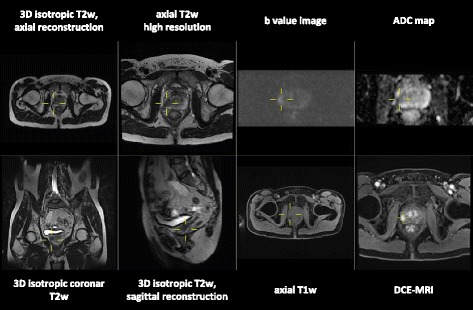

Ideally two 21.0 inch or one 30.0 inch standard radiology monitor for image display with a resolution of at least 3 megapixels and a contrast ratio of at least 750:1 should be available. Additional monitors for reporting and other activities e.g. PACS steering, Internet, reference databases are recommended. Depending on the software, which is used, morphologic and functional sequences should be displayed at the same time. For a first overview axial T2w images are recommended. On the left side we display the morphologic T2w images. On the right side DWI is displayed, i.e. b-value images and ADC-map at the same time. Ideally the morphologic and the functional images should be linked at the same table position. With this described display mode, in many cases a final diagnosis of the primary tumour can already be made according to PI-RADS™ v2. In addition, DCE-MRI is displayed in a continuous stack of images at different time points and table positions. For exact morphologic localisation of suspicious lymph nodes and level of the prostatic lesion isotropic voxel 3D T2w sequence can be reformatted at user's preferences [14]. Additionally fused images of morphology and functional maps may be helpful for exact localisation of findings. A standard layout of our prostate image display is shown in Fig. 2.

Fig. 2.

Standard layout of our prostate image display in a one screen setting. Double clicking in one of the images allows to display this image in full screen mode